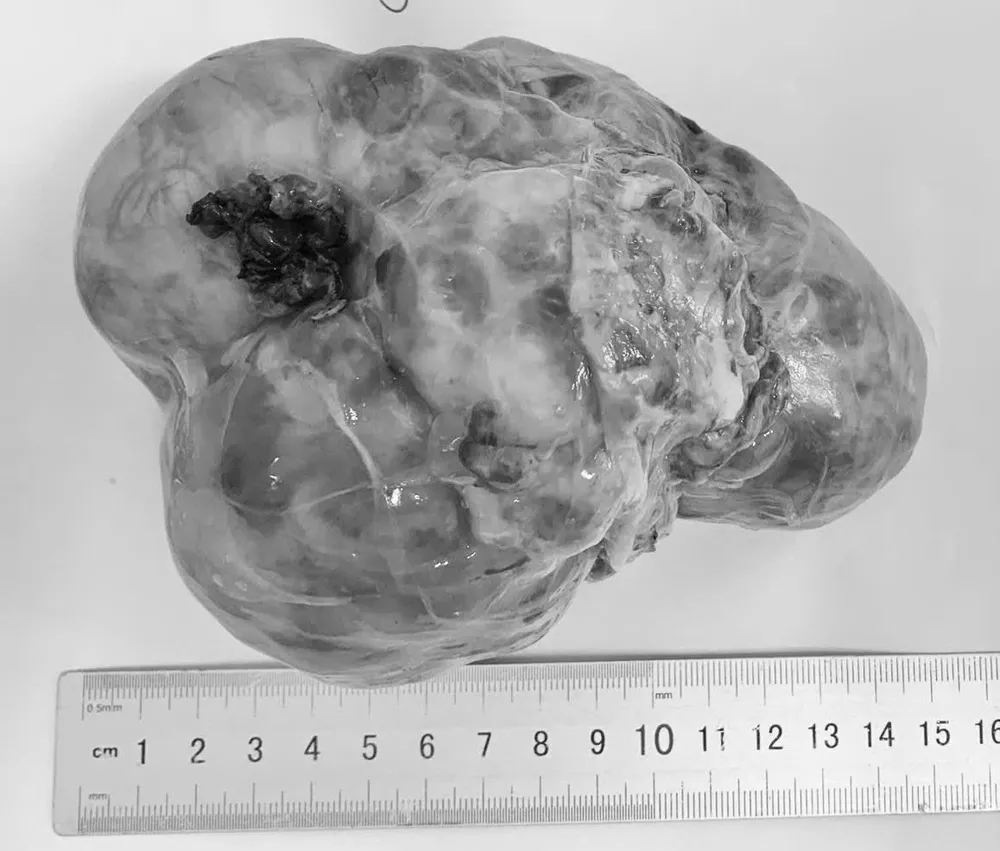

Khối u ổ bụng được phát hiện trong quá trình phẫu thuật cho bệnh nhi

Nhiều trường hợp vừa qua, khi nhập viện, khối u ở các bệnh nhi đều đã có kích thước lớn, làm tăng độ phức tạp của phẫu thuật và ảnh hưởng đến quá trình điều trị lâu dài.

Tất cả các trường hợp đều được phát hiện khi tuổi còn nhỏ nhưng khối u đã phát triển lớn hoặc đã di căn.